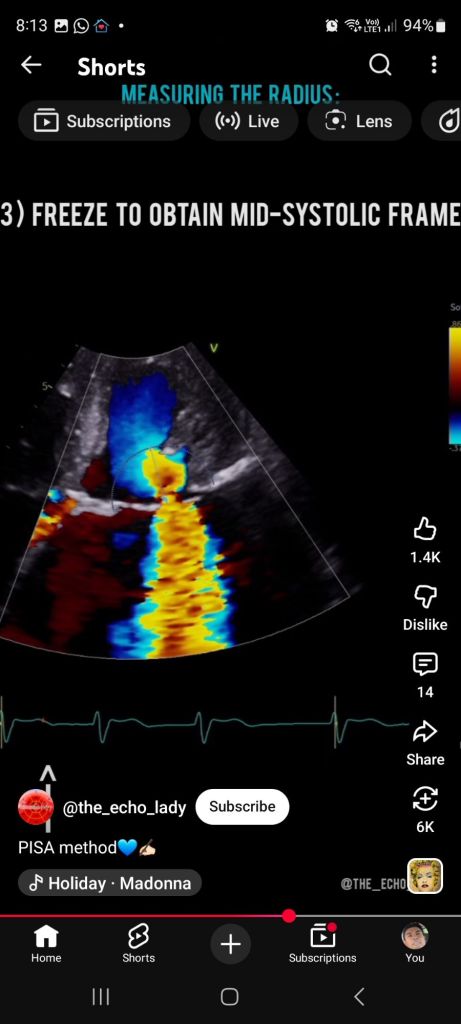

On color Doppler:

Flow suddenly changes color (e.g. red → blue)

That sharp boundary = aliasing velocity line